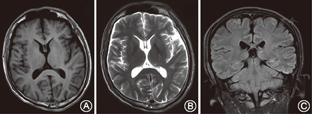

所调查的家系成员共15名,发病患者7例,均发现有肢体无力症状,MRI证实有脊椎多发的椎管内神经纤维瘤,而其他成员MRI均未发现椎管内神经纤维瘤。患者均无咖啡牛奶斑、虹膜Lisch结节、脊柱侧凸,无内脏肿块压迫出血症状,无耳鸣、听力下降,头晕,无持续性头痛、恶心、呕吐和视物不清等颅内压增高等临床表型(图1)。先证者(Ⅲ9)的MRI示左侧丘脑可见小斑片状长T1长T2信号,T2WI-FLAIR呈高信号;余双侧侧脑室旁白质内可见条状或类圆形长T1长T2信号,T2WI-FLAIR呈低信号;部分脑沟、池、室增宽。提示左侧丘脑高信号小病灶,轻度脑腔隙,轻度脑萎缩(图2)。双侧颈胸腰椎椎间孔及骶管扩大,双侧颈、胸、腰及骶神经根走行区见多发串珠状、丛状、囊状类圆形或梭形病灶,边界较清,长T1长T2信号,压脂T2像呈高信号。较大者位于颈1~2双侧椎间孔区,右侧较大,约2.5 cm×2.1 cm×1.8 cm,部分长入局部椎管内,明显压迫局部硬膜囊及脊髓。颈5~6右侧椎间孔区病灶部分长入椎管内右侧部,大小约1.3 cm×1.1 cm×1.8 cm,压迫局部硬膜囊及脊髓,向左侧移位。胸12至腰1左侧椎间孔区病灶部分长入局部椎管内,矢状位约0.9 cm×1.0 cm,局部脊髓圆锥稍受压移位。扫描区内胸腰背部皮质及部分肌肉间隙内见多发病灶,呈等T1等T2信号或长T1长T2信号,最大径约2.6 cm(图3)。颈1~2椎管外、颈5~6椎管内肿瘤切除术后病理:节细胞神经瘤(图4)。免疫组织化学:Ki67(1%+),S100(+++),神经元特异性烯醇化酶(节细胞+),Neu-N(节细胞+),Nf(节细胞+),SY(节细胞+)(图5)。